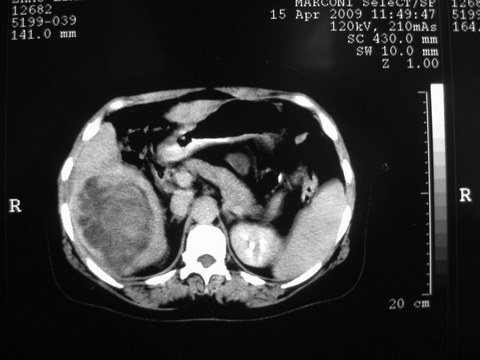

患者 女 51岁 两天前感觉上腹疼,无明显诱因,b超示肝右叶囊实性占位,边缘清楚,其内回声不均匀,ct增强如图,大家看看是什么 ,病人一年前及两月前b超检查只是提示胆囊炎

外院术后,证实肝癌合并出血

特点:1,病灶发展迅速,(2月前正常)[br] 2,囊实性,且并边界清晰光滑,呈右后叶赘生性。囊性区无强化,实性部分较多轻度强化,边界欠清。考虑囊腺癌或囊腺瘤。

出病理 中分化肝细胞癌合并出血